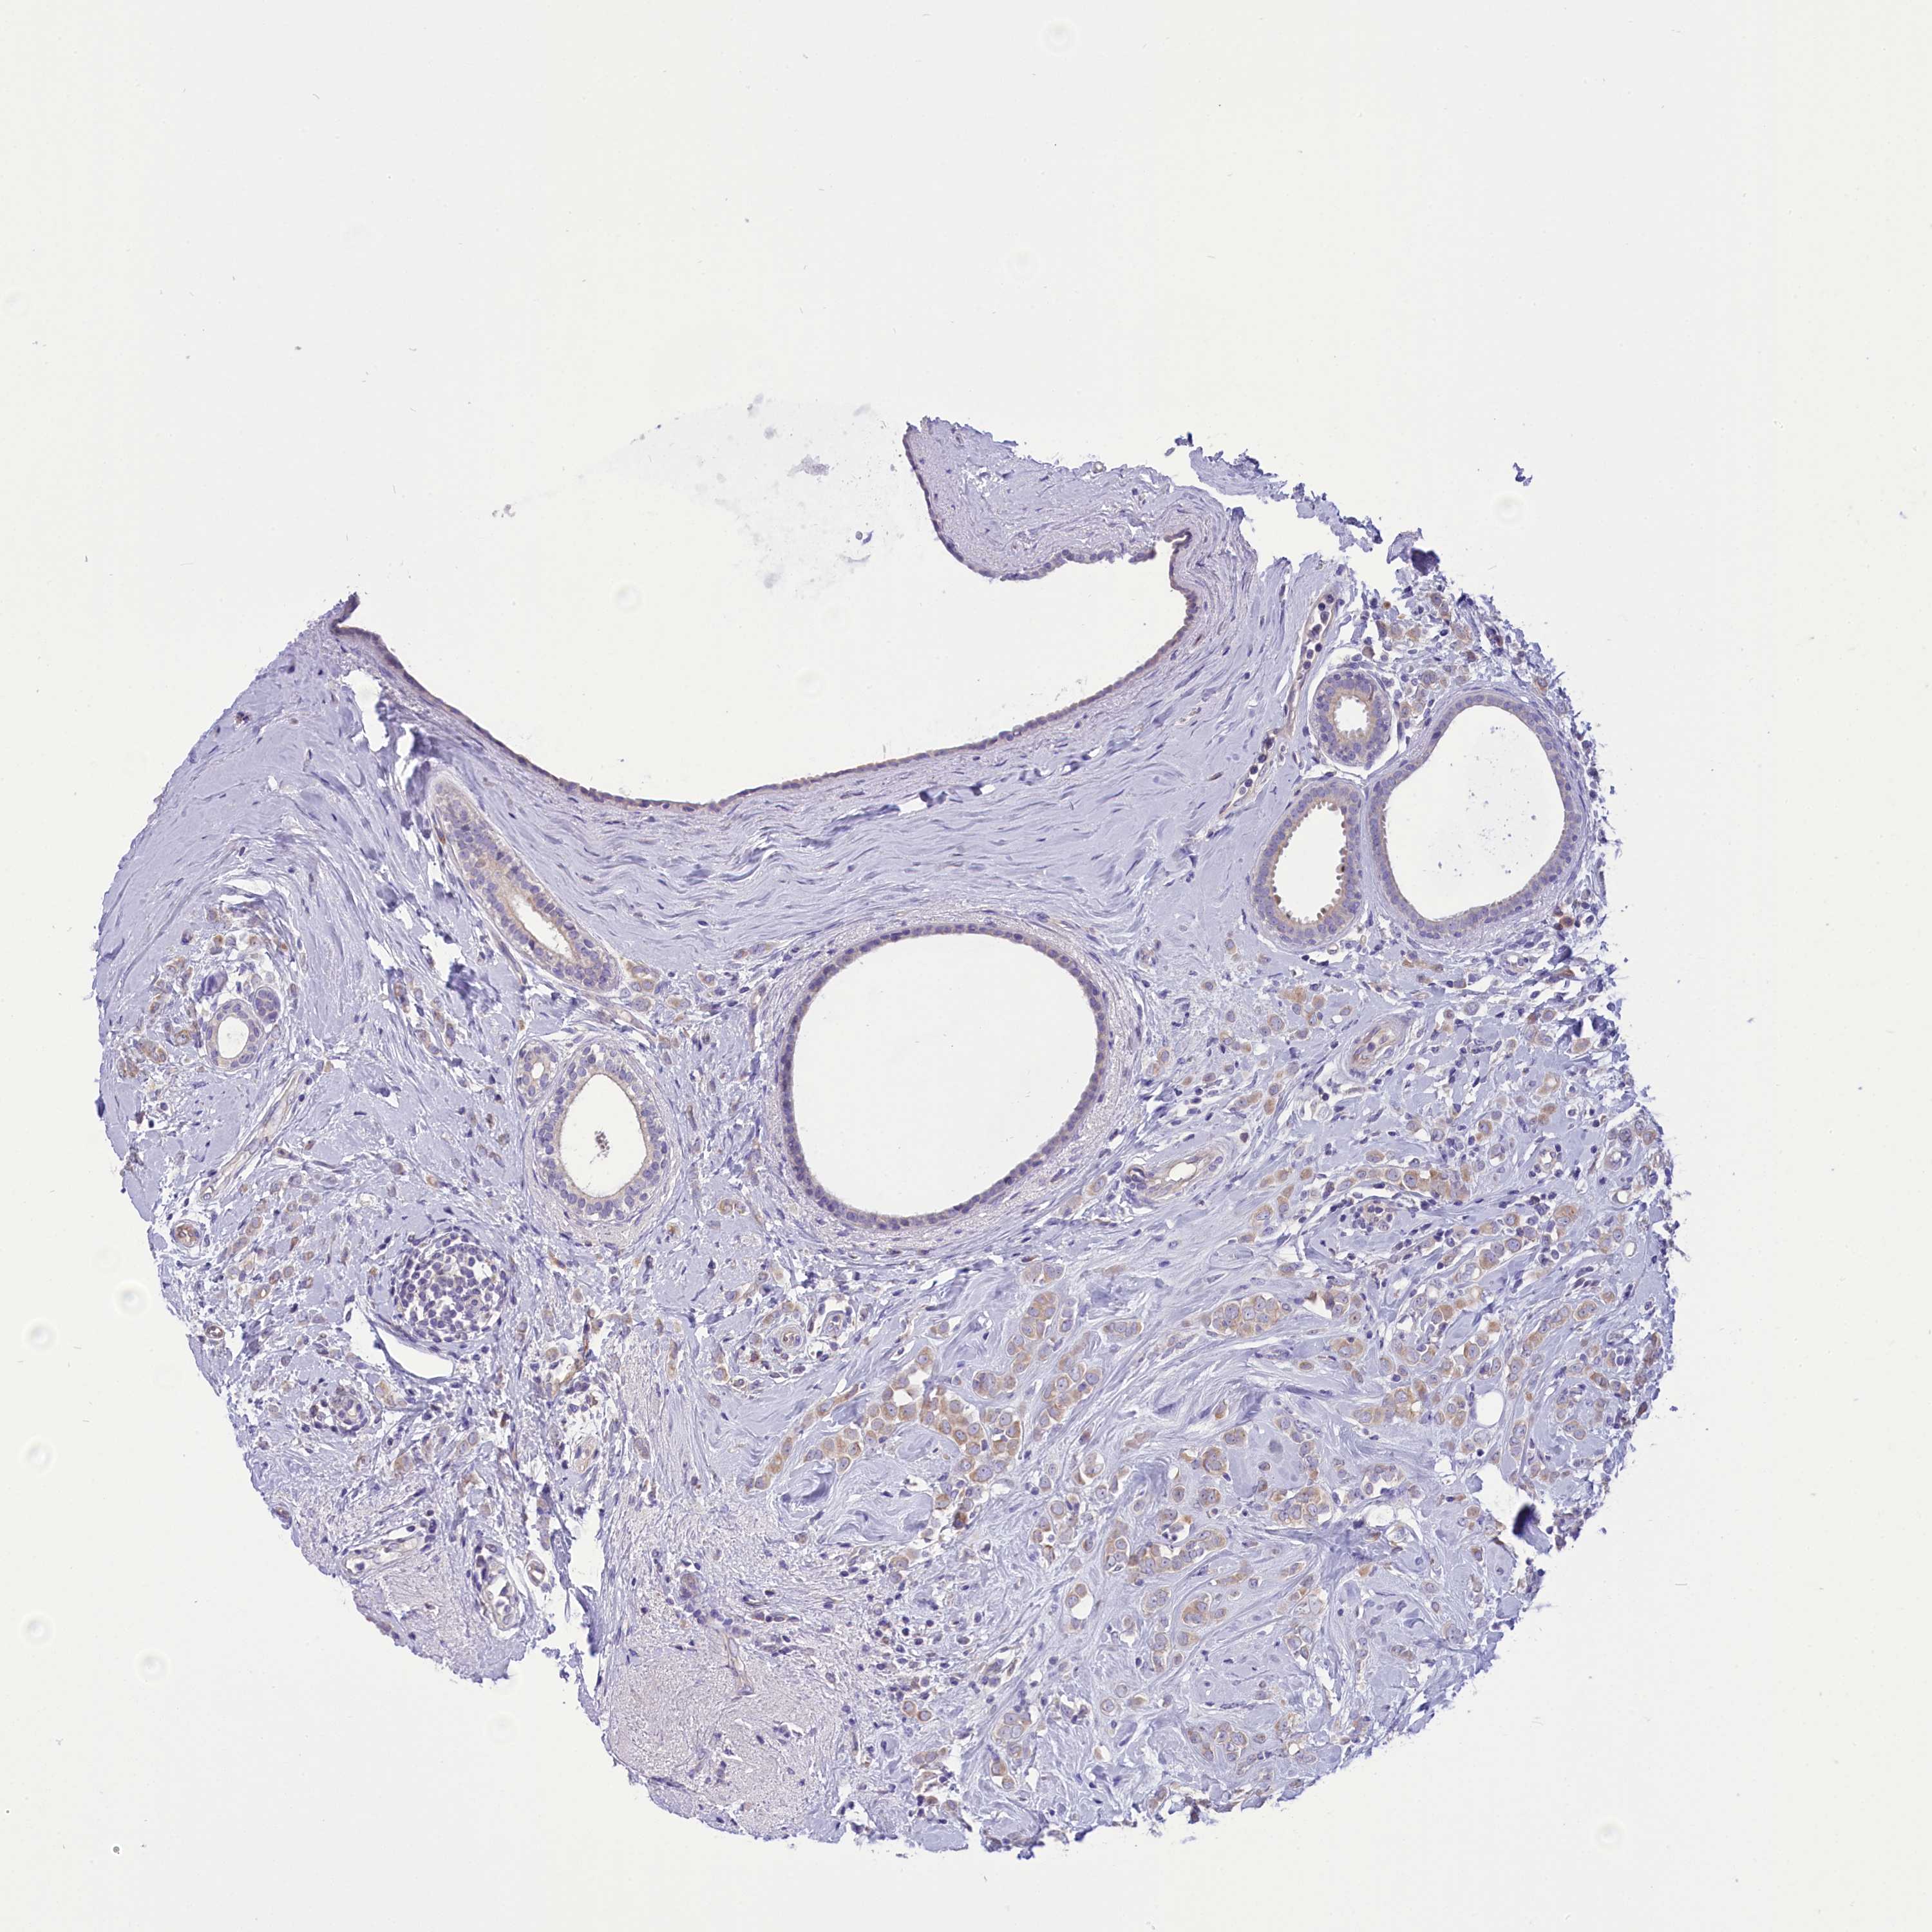

BRCA TCGA BRCA VALIDATION PROTEIN EXPRESSION